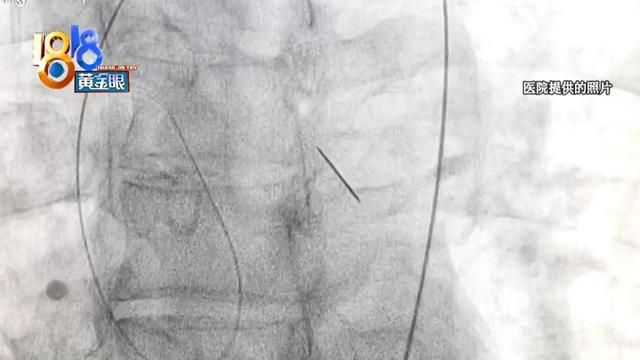

从绍兴当地医院提供的片子看,杨师傅左支气管里有异物。考虑到他有吃鱼的习惯,一开始,医生怀疑这是一根鱼刺。4月26号,杨师傅被转到浙大邵逸夫医院,他表面上看起来没什么异样,结果在诊室里又突然开始咳血。

后来,医院采用支气管镜介入,清理掉气道里大量的血块凝结,异物慢慢地露出了原貌,大家都吓了一跳,竟然是一根针。

当时这根针已经刺穿杨师傅的胸降主动脉和左支气管,随时有大出血的危险,严重的会导致休克,甚至是死亡。最保守的取针方式,是通过开胸手术,这能让所有风险都看得见,但如果这样做,给患者带来的创伤将非常大。经过多学科研讨,最后医院从杨师傅的口腔介入,分四次取出异物。

手术持续了两个小时,取出的这根针长3.6厘米。